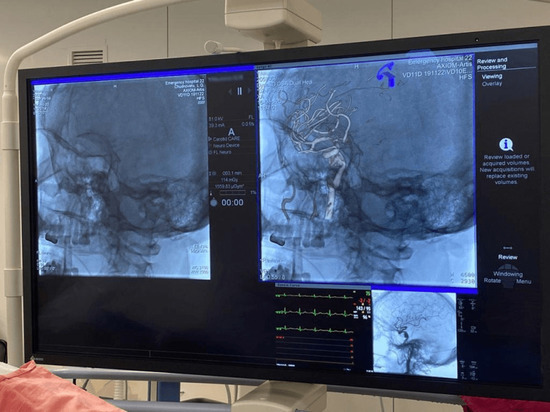

В столице Башкирии врачи больницы скорой медицинской помощи провели уникальную операцию, установив потоковый плетеный стент особой конструкции в артерию на уровне аневризмы в голове пациента.

Процедуру провели с помощью нового ангиографа, который в больницу поставили в рамках нацпроекта «Здравоохранение».